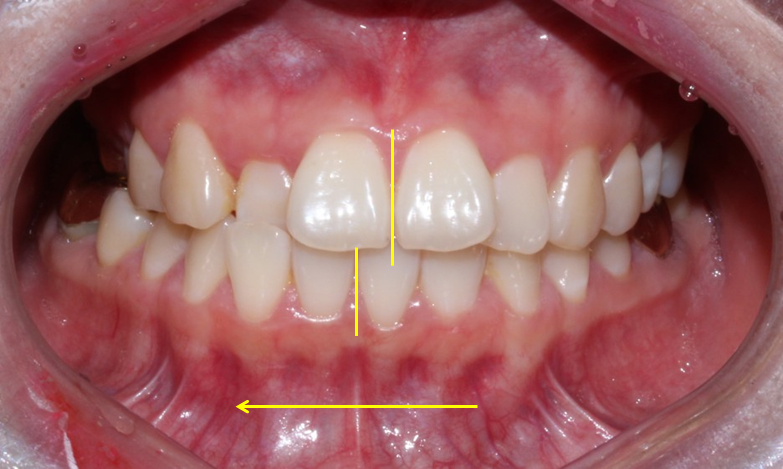

왜 이렇게 물리는가 ? 보면

아래턱 자체가 오른쪽으로 돌아가있는

골격적 구조를 가지고 있습니다.

위 중심선은 괜찮지만

아래 중심선이 우측으로 치우쳐 있고

(사진상 왼쪽으로)

그러다보니 당연히

오른쪽은 조금더 반대로 물리는 성향을

띄게 되겠죠?

골격적 비대칭으로 인해 좌우 높이도

많이 달라보입니다.